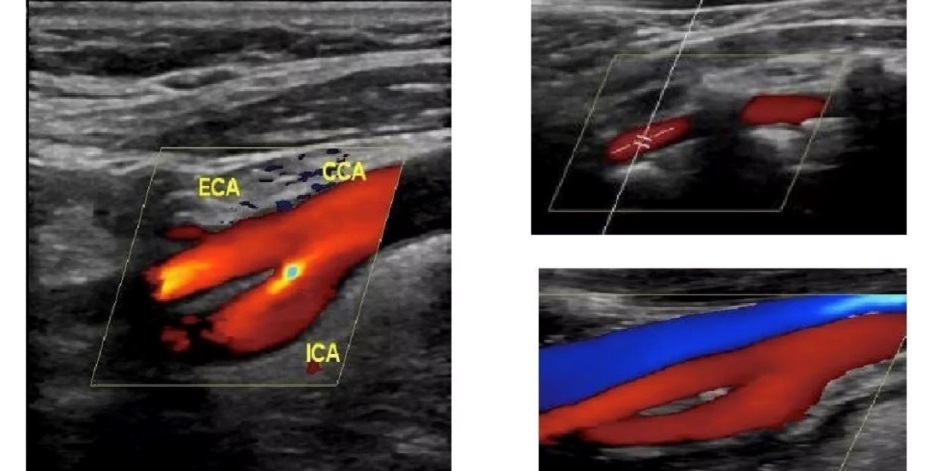

彩超图像的颜色代表什么?

彩色多普勒技术主要用红色蓝色来显示组织器官内血液的不同流向,颜色的不同能够帮助超声医生分辨血液在哪个方向流动;如果血液的流动方向朝向探头,图像显示为红色如果血液的流动方向背向探头,则图像显示为蓝色。另外,图像显示为红色、蓝色与动静脉分类无关哦。